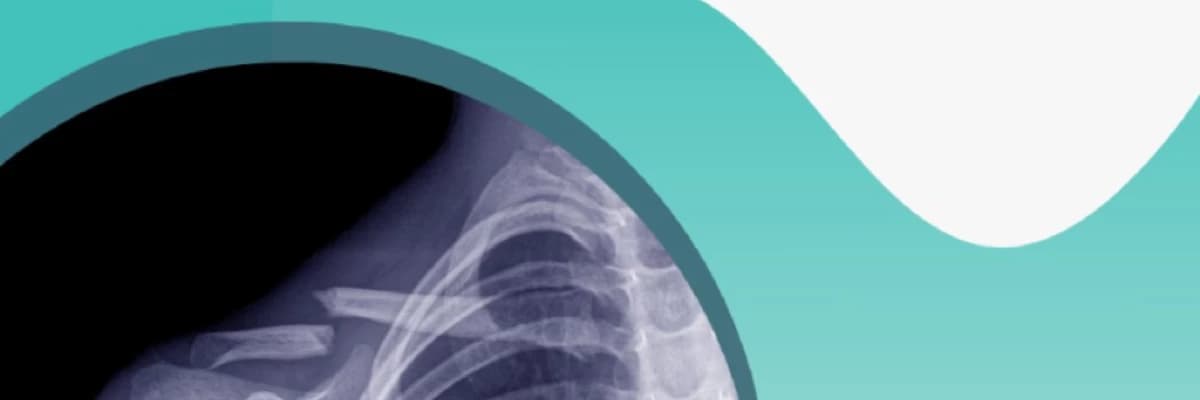

Klavikül Kırığı

Klavikül kırığı, klavikula adı verilen köprücük kemiğinde meydana gelen kırıkları ifade eder. Bu kırıklar genellikle düşmeler, spor yaralanmaları veya trafik kazaları gibi travmatik olaylar sonucunda ortaya çıkar.

Belirtiler arasında omuzda ağrı, şişlik, morarma ve kırık bölgede hassasiyet bulunur. Tedavi genellikle istirahat, atel kullanımı, ağrı yönetimi ilaçları ve fizik tedaviyi içerir. Bazı durumlarda, kırık ciddiyetine bağlı olarak cerrahi müdahale gerekebilir.